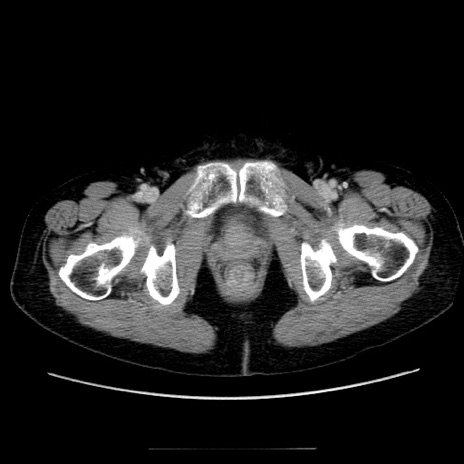

症例5(横断像)

【症例】70歳代女性

【主訴】お腹が張る

【現病歴】1週間くらい前から腹部膨満の自覚あり。昨日夜から増悪したため、本日救急外来受診。

【身体所見】意識清明、BT 36.5℃、BP 165/106mmHg、HR 80bpm、SpO2 98%、腹部:膨満、軟、自発痛・圧痛なし、触診にて不快感あり、腸蠕動音:減弱

【データ】WBC 12600、CRP 1.04